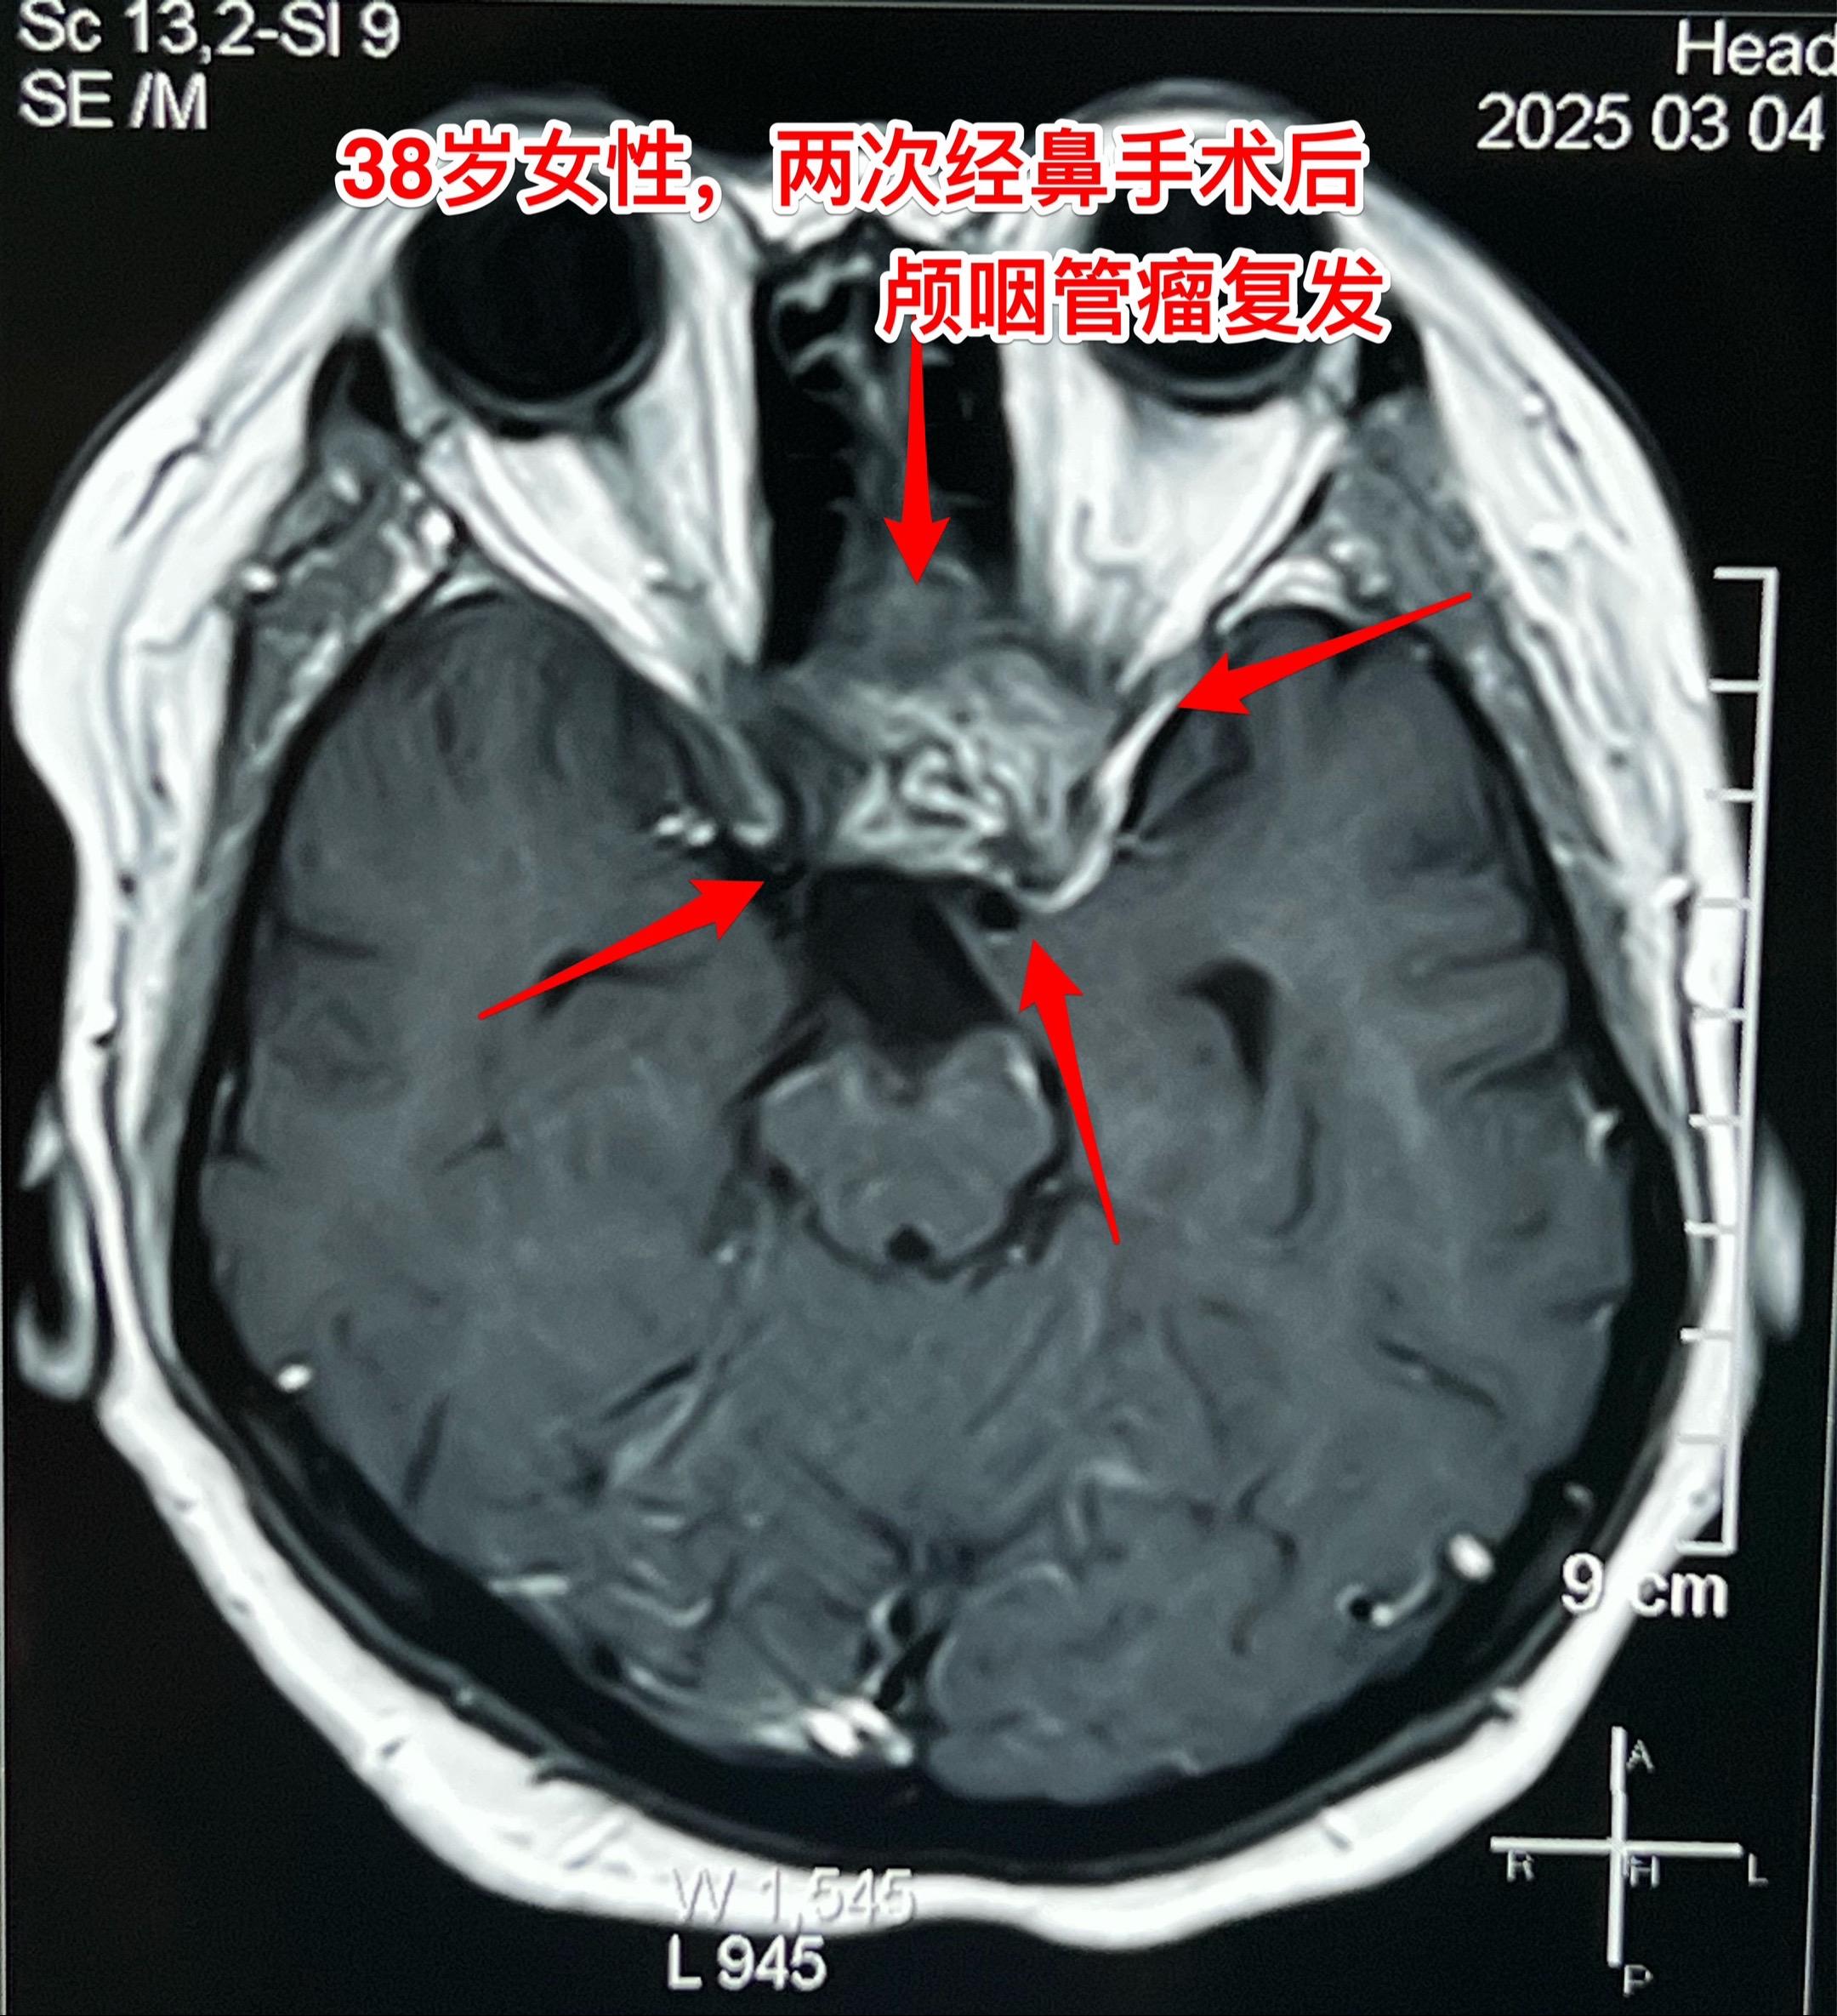

昨天的第四个手术(经鼻复发颅咽管瘤)昨日第四个完成的手术,是38岁女性,因为颅咽管瘤在北京某军医院先后作了两次经鼻内镜手术切除肿瘤。过年后发现肿瘤又复发了,见图。病人的左眼视力很差,属于无效视力。 手术结束时已是今日凌晨了!肿瘤从垂体窝向左侧生长,得到完全切除! 今日头部CT结果是满意的,病人从ICU转回了普通病房。希望肿瘤不再复发。